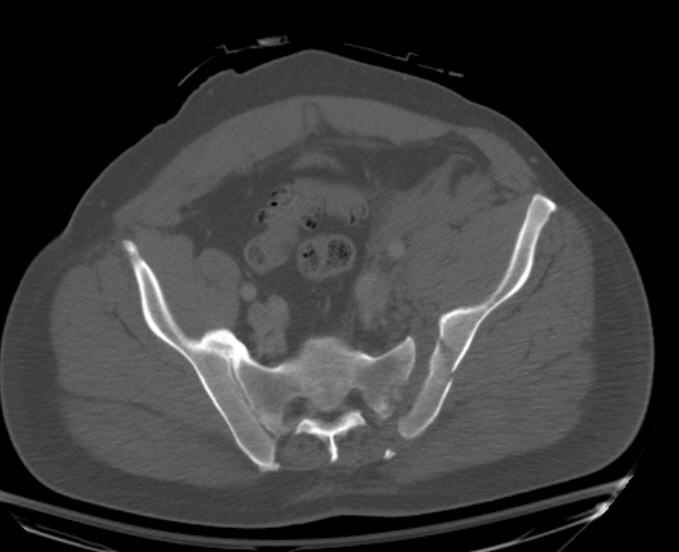

Hello gentlemen- Case is 52 YO male, fell out of treestand while deerhunting. He is 6 ft, approx. 260-275 lbs. Was hemodynamic unstable at local ER, sent to our Trauma center where circumferential pelvic binder placed and pt. stabilized with fluid, blood, and rewarming. Angiography not performed. An extraperitoneal bladder disruption was found, uro elected to treat non-operatively. Initial xray (not shown) demonstrated 5-7 cm wide at symphysis and SI joint. The first image attached is of CT once binder is in place. On post trauma day 5 the pt was taken to OR for ORIF of his iliac wing fracture and SI dislocation. The swelling/3rd spacing of fluid in the area of symphysis was profound, but quite acceptable posteriorly. Patient was prone for procedure, as I thought too difficult to fix the wing in lateral position. Of course the repair of wing was easy, but reduction of SI very demanding. The Floro images document the residual lack of reduction. That was the closest I could get it using 6mm joystick in wing, and clamp on sacrum and clamp through notch. The fixation was (initially) rigid. Anterior ex fix with supra-acetabular pins was placed due to condition of soft tissues, massive "beer-belly" overhanging the crest. Post trauma day ten patient's xray shows failure of posterior construct. Plan was to perform revision orif once soft tissues resolve considerably for full anrterior fixation and posterior fixation. However, while Im away for holiday (on Post trauma day 15), pt is developing septic clinical appearance, and trauma suspects pelvic abcess near symphysis and performs I and D - finds nothing but no primary closure performed. Posterior tissues/incision continue to look healthy. Now is post trauma day 17, pt is still tubed/on dopamine/and wbc still elevated, anterior incision still packed open. Clearly must get to bottom of possible sepsis, but then what? Thanks for you time - sorry for such lengthy clinical description. Thomas Schaller Kalamazoo, Michigan

Request for more images.. Axial and coronal recon (pt in binder.)